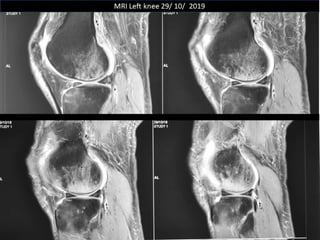

The document presents a detailed case study of a patient with transient osteoporosis of the hip (TOH) and spontaneous osteonecrosis of the knee (SONK) treated at Choithram Hospital & Research Centre in India. Over 20 years, the patient experienced multiple episodes of TOH and SONK with no history of trauma or co-morbidities, resulting in resolutions and recurrences of conditions. The information is intended for orthopedic surgery students and highlights personal experiences and case collections, with a disclaimer regarding content usage and potential controversies.